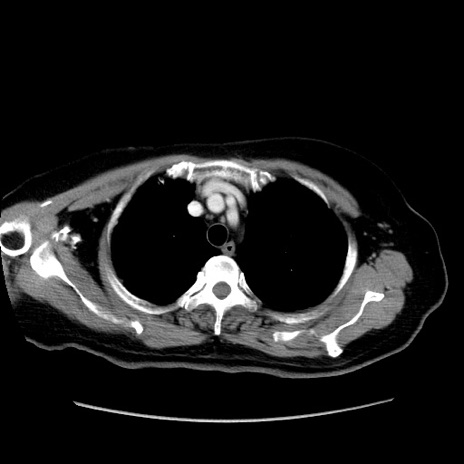

症例19(横断像)

【症例】80歳代女性

【主訴】下腹部痛

【現病歴】約8時間前より下腹部痛の出現あり、救急外来受診。

【既往歴】両側付属器切除

【身体所見】意識清明、下腹部正中に手術痕あり、その部位に一致して圧痛と反跳痛あり。腸蠕動音は亢進。

【データ】WBC 9300、CRP 0.15